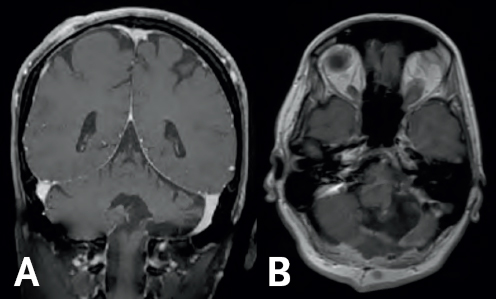

(Left) Gray colored variations are enclosed by a white outline. There is a dark gray column at the bottom of the image in the middle connecting the gray area to the bottom of the image. (Right) Gray and white colorations are depicting normal brain structures; all are surrounded by a white boarder.

FIGURE 6.2 Two-year Follow-up MRI. Post-operative coronal (A) and sagittal (B) MRI continues to demonstrate no evidence of tumor recurrence following her original gross total resection.

The prognosis for GBM is generally poor—the median survival is roughly 12 months after diagnosis.7 Incredibly, Jane has continued to defy all odds following the surgery. Her most recent MRI, now three and half years following the procedure, continues to demonstrate no evidence of any residual or recurrent tumor (Figure 6.2). As a cancer survivor, Jane continues in her courageous battle against NF1. Her determination in the face of adversity remains a source of inspiration for her friends, family members, and providers.